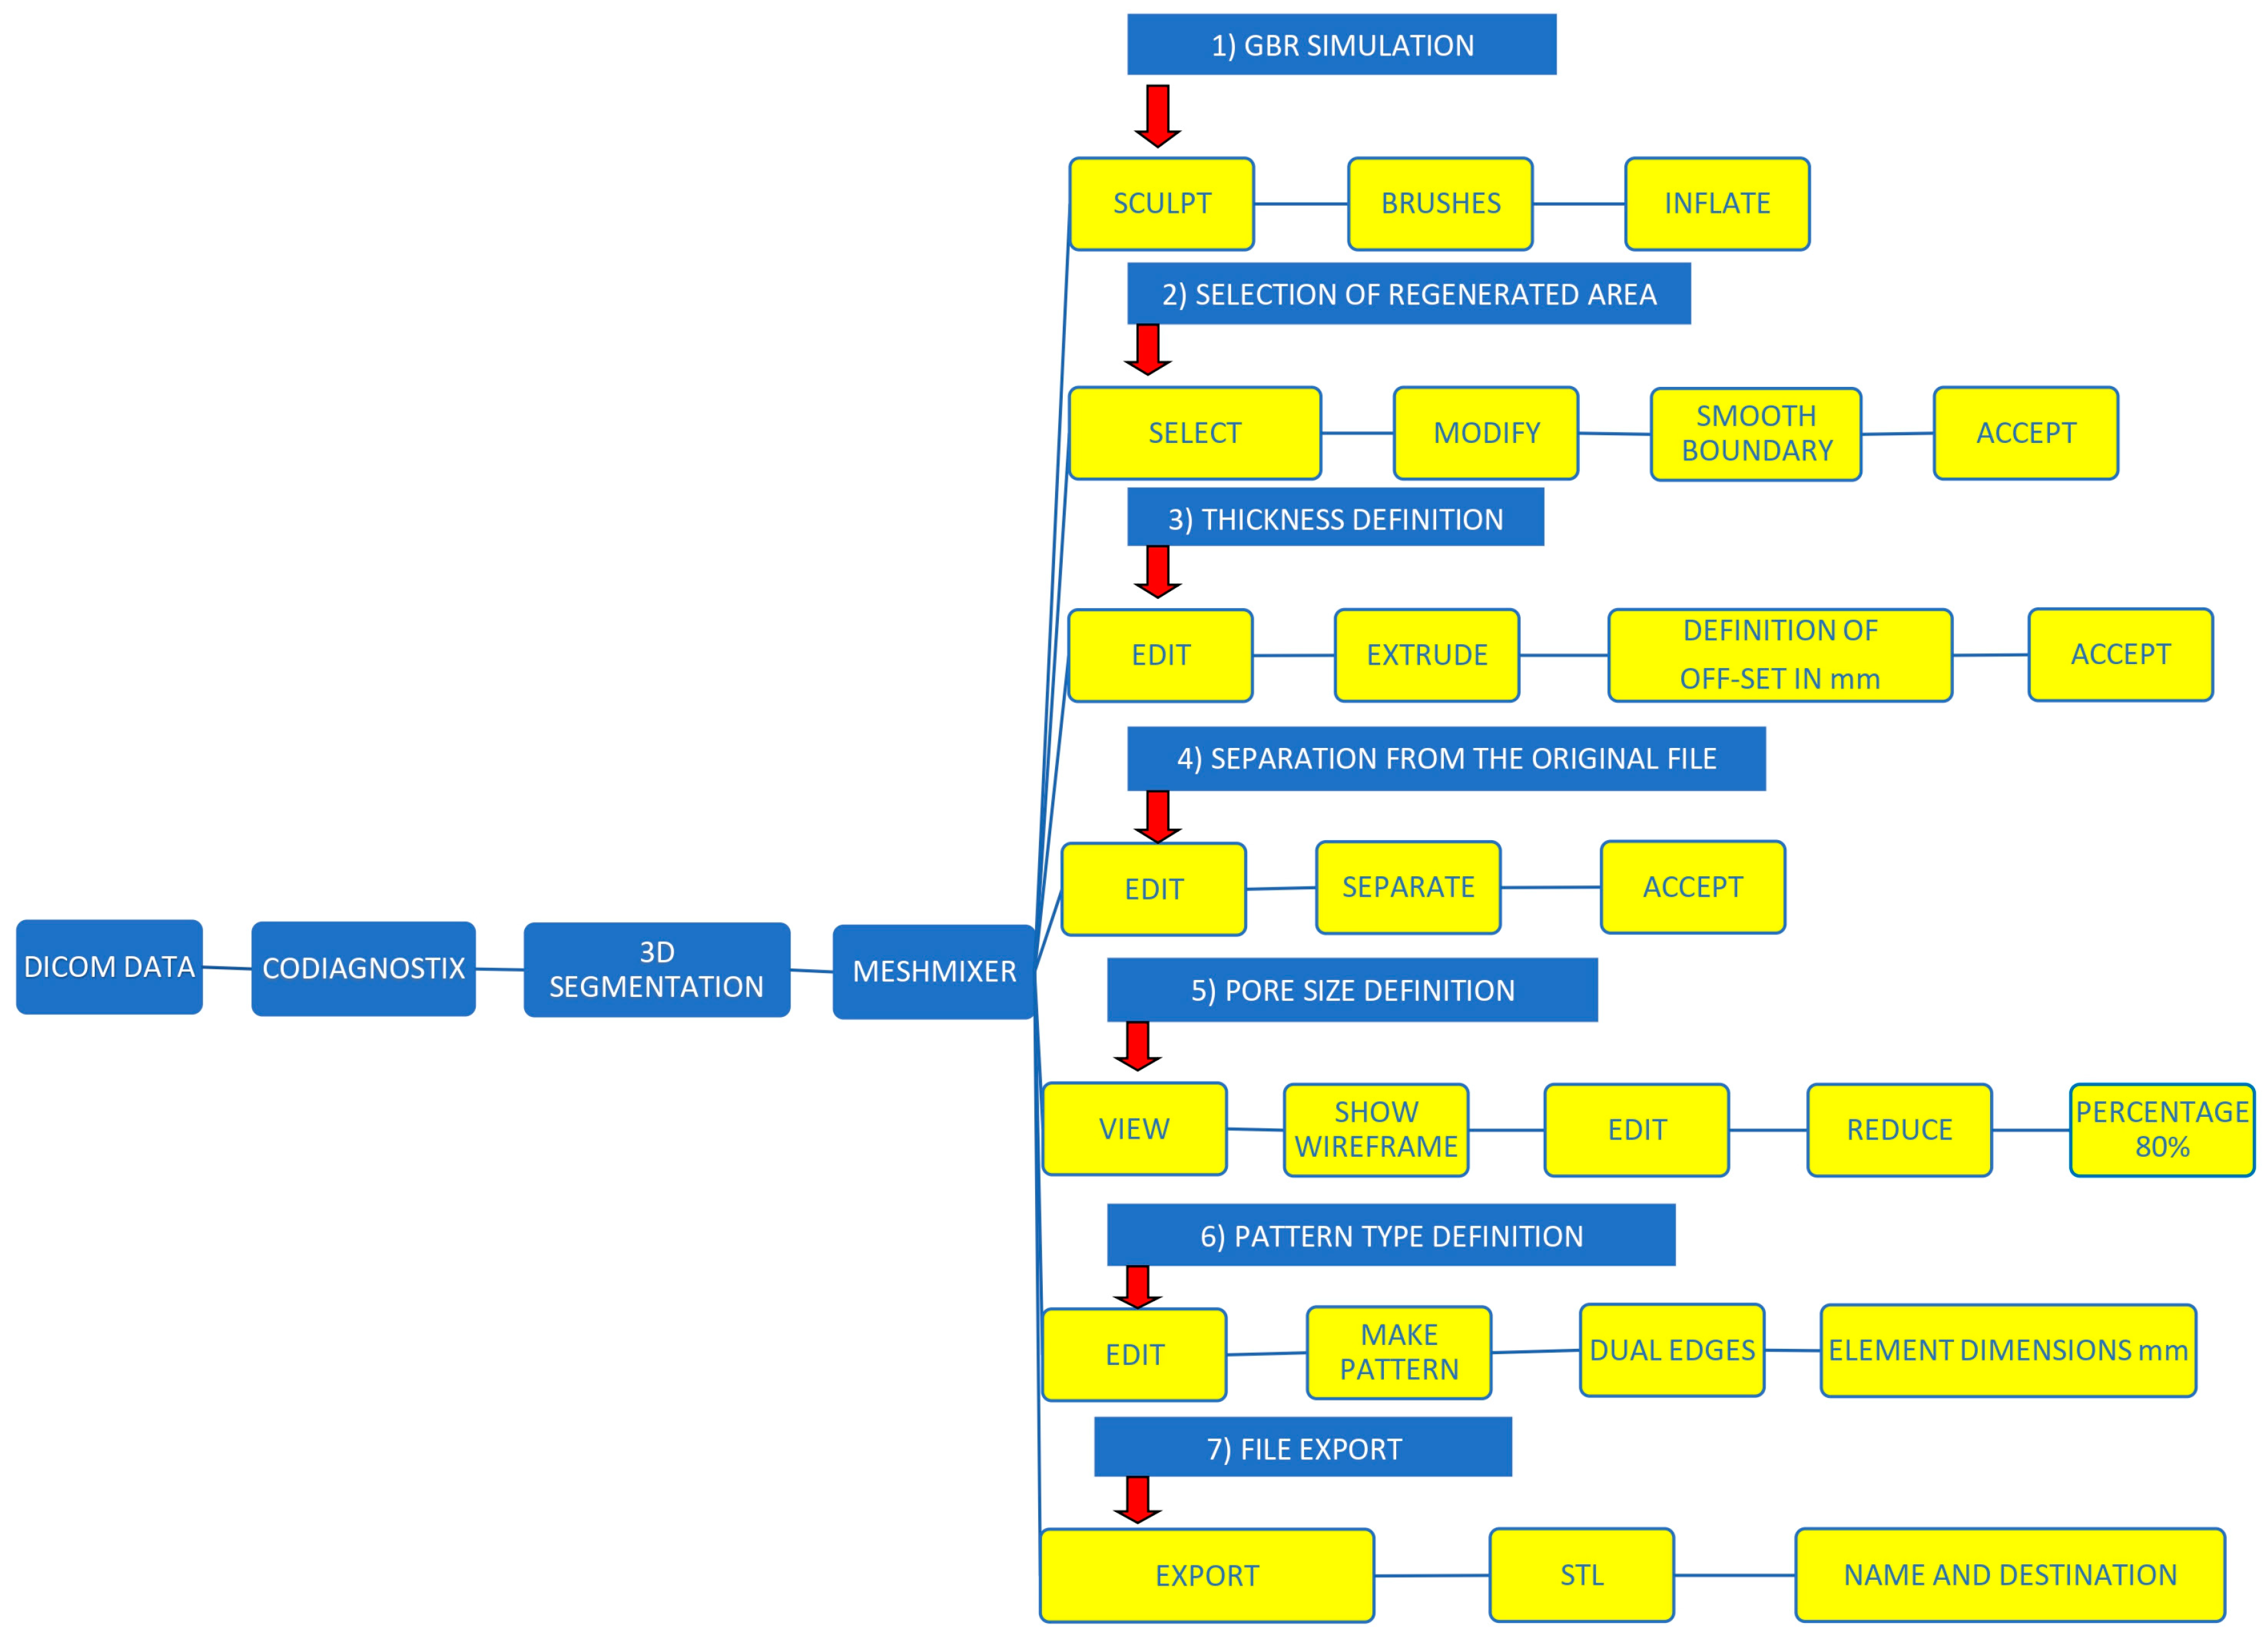

2.2. GBR Simulation and Mesh Design